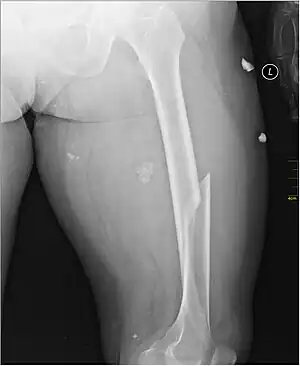

X-ray image of a femoral shaft fracture

A femoral fracture is a bone fracture that involves the femur. They are typically sustained in high-impact trauma, such as car crashes, due to the large amount of force needed to break the bone. Fractures of the diaphysis, or middle of the femur, are managed differently from those at the head, neck, and trochanter; those are conventionally called hip fractures (because they involve the hip joint region). Thus, mentions of femoral fracture in medicine usually refer implicitly to femoral fractures at the shaft or distally.

Radiography

Anterior-posterior (AP) and lateral radiographs are typically obtained.[4] In order to rule out other injuries, hip, pelvis, and knee radiographs are also obtained.[5] The hip radiograph is of particular importance, because femoral neck fractures can lead to osteonecrosis of the femoral head.[4]